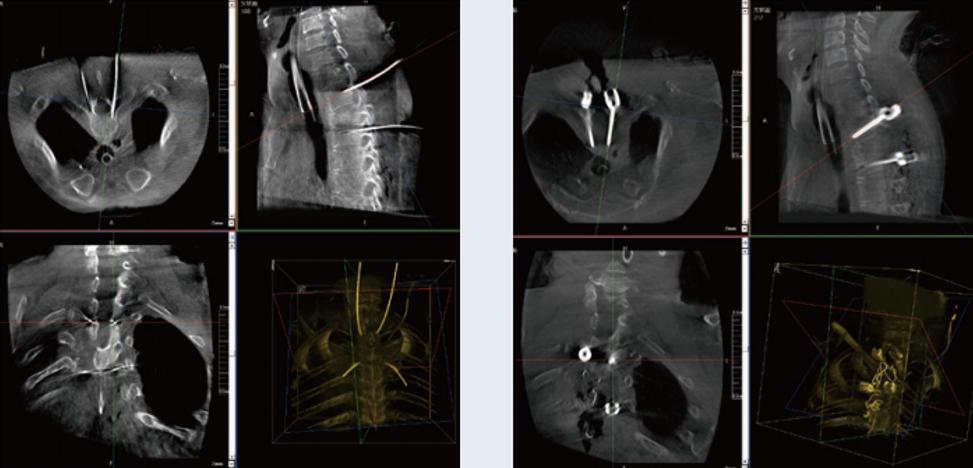

螺釘規(guī)劃后的圖像

植入螺釘后的圖像

術(shù)中三維C臂與骨科導(dǎo)航機(jī)器人配合應(yīng)用,實(shí)現(xiàn)準(zhǔn)確定位,確保了手術(shù)安全、高效完成。術(shù)后二維、三維影像顯示手術(shù)效果良好,達(dá)到預(yù)期目的。

普愛醫(yī)療三維C臂提供了高質(zhì)量的術(shù)中實(shí)時三維圖像數(shù)據(jù),保障了骨科導(dǎo)航機(jī)器人手術(shù)的準(zhǔn)確度和安全性,取得不錯的手術(shù)效果。同時,三維C臂特有的斷層成像,能幫助醫(yī)生在術(shù)中非常直觀地判斷螺釘植入的準(zhǔn)確度。